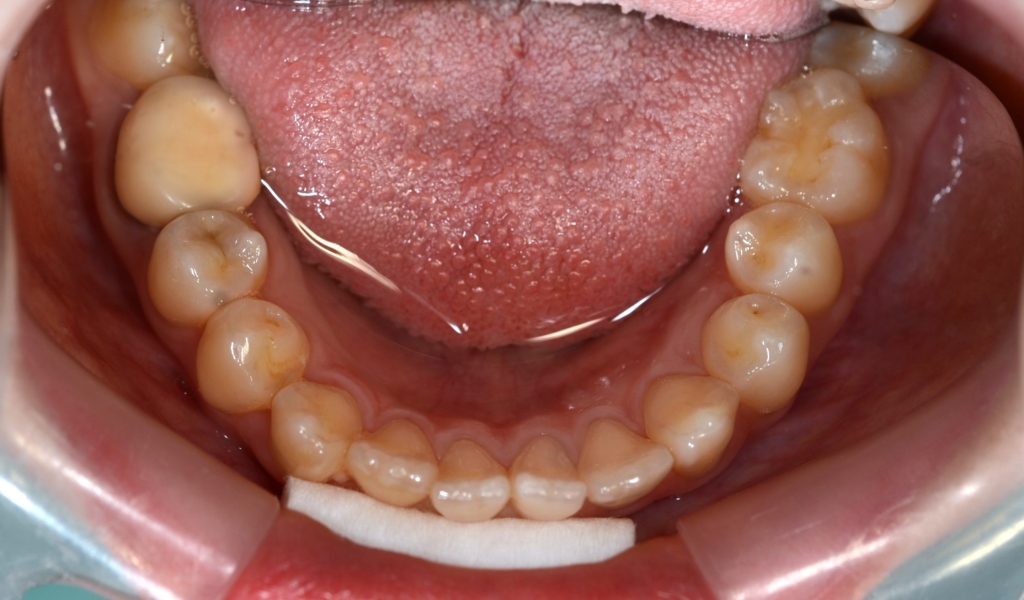

ついでに、歯並びの比較です

上段が矯正治療前、下段が矯正治療後